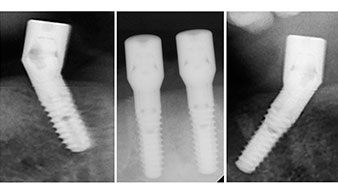

A three-dimensional cone beam computed tomography scan (CBCT, Planmeca) was performed to aid planning and minimize risks. This revealed that the quality and quantity of the available bone were sufficient for the surgery and immediate restoration using the Fast & Fixed method. Following the protocol for this concept, the implants are inserted at 35, 32, 42 and 45. Angling the distal implants by up to 45° shifts the emergence profile to posterior and generates a larger support polygon (Fig. 3).

Angled abutments (35°) were screwed in to compensate for the divergence of the distal implants, with the result that the emergence profile of all implants was as perpendicular as possible to the bite plane. This is a prerequisite for occlusal placement of the provisional and subsequently the permanent denture (Fig. 15 and 16).

The impression and bite registration were then performed so that the dental technician could begin producing the provisional restoration immediately. This was then screwed in on the same day (Fig. 17 and 18).

Following the time required for the osseointegration, the final impression of the implants could be performed and the final denture produced accordingly (Fig. 19 and 20). At this point, the dentist and patient were able to decide together whether to use a ceramic or acrylic veneer and a zirconium or metal framework. In this case, Dr. Pascu’s team decided on an acrylic veneer based on the unclear prognosis for the maxillary dentition and the fact that tooth 24 is elongated. This type of veneer is generally considerably easier to adapt and can thus be subsequently altered to reflect the new situation in the maxilla.